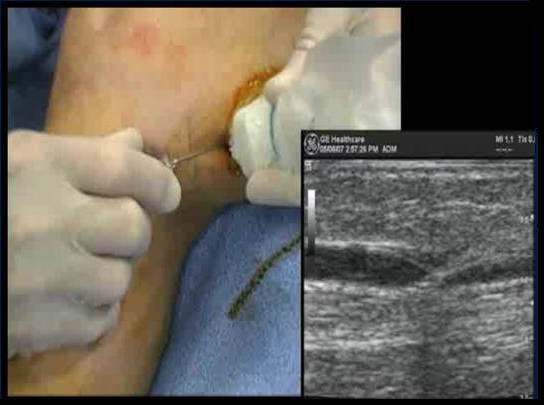

ПРОВЕДЕНИЕ ПРОЦЕДУРЫ

• Игла диаметром 18G

• Интродьюсер 7fr, 11 см

Оптимальное расположение кончика катетера - на 2 см дистальнее СФС

Плотная перивенозная инфильтрация по всей длине катетера

ФИНАЛЬНЫЙ КОНТРОЛЬ ПОЛОЖЕНИЯ КОНЧИКА КАТЕТЕРА

Под контролем УЗИ убедитесь, что кончик катетера расположен на 2 см дистальнее СФС